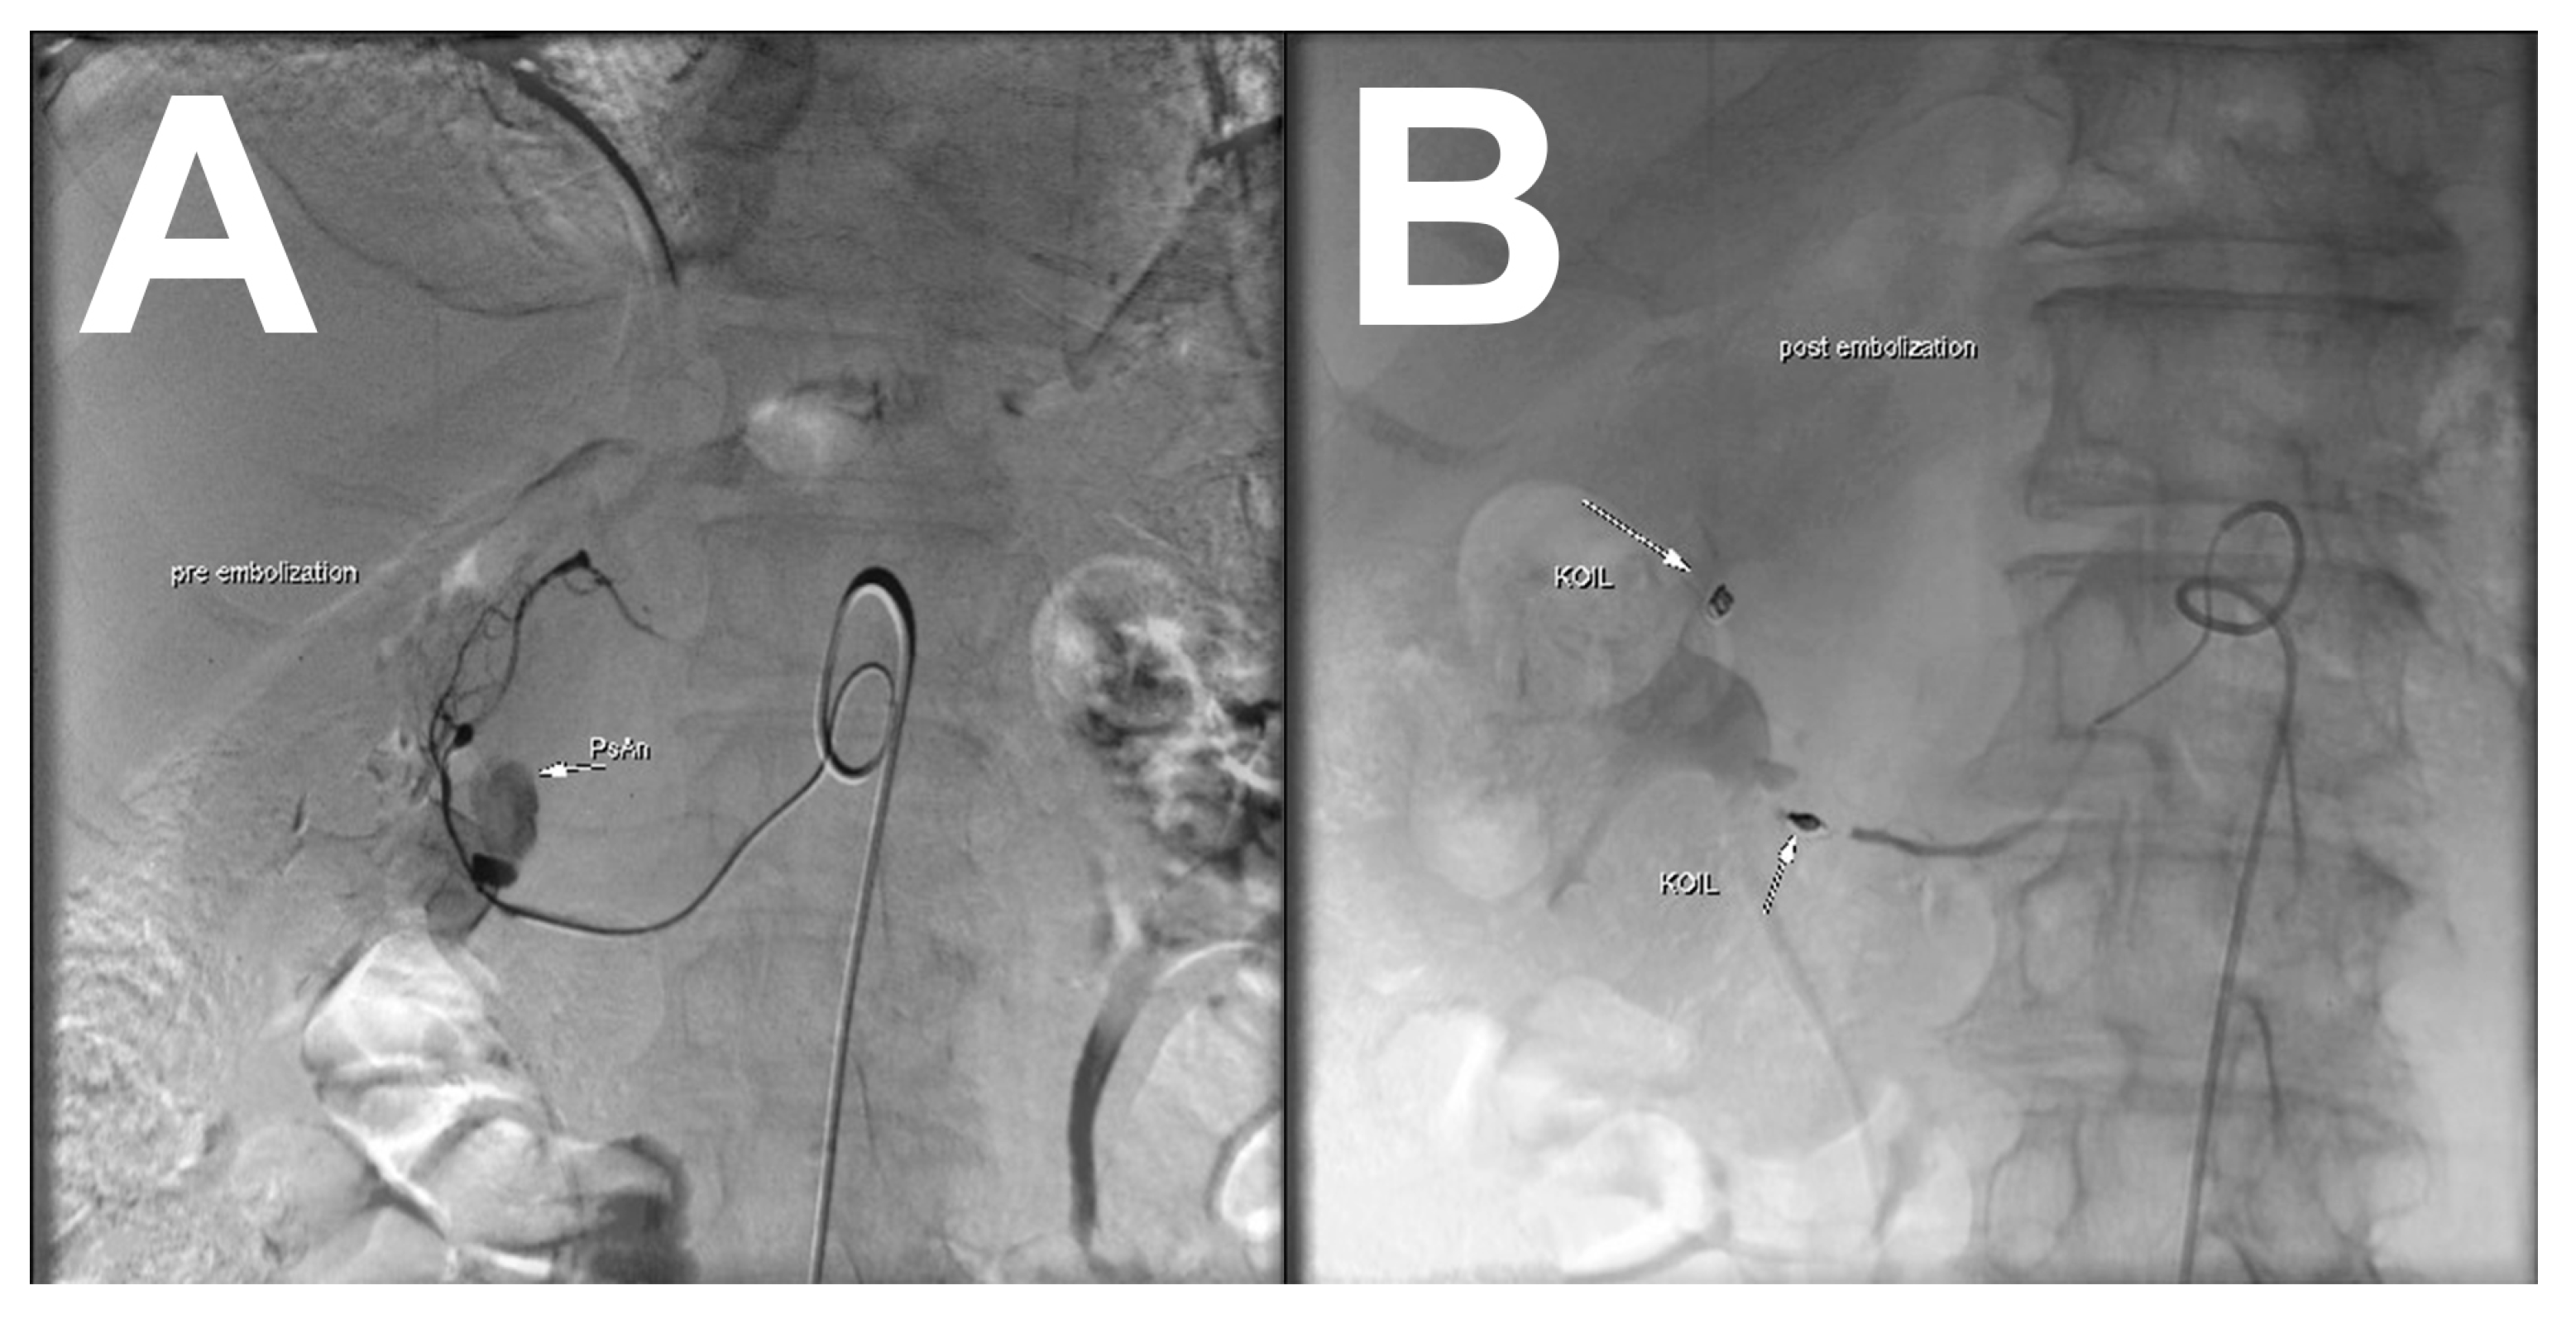

Successful Embolization of Posterior Inferior Pancreaticoduodenal Artery Pseudoaneurysm on the Grounds of Chronic Pancreatitis—Case Report and Literature Review

2. Case Report